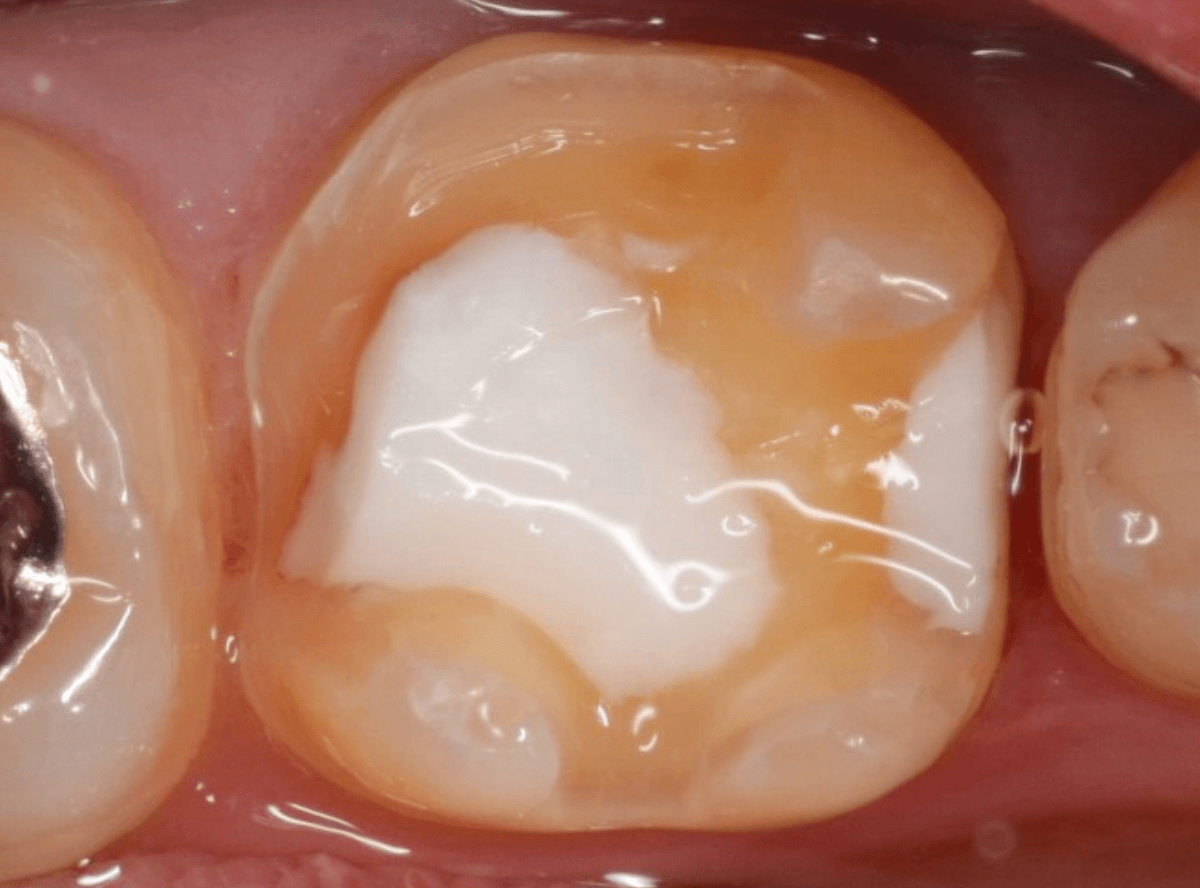

set後の写真です。

患者さんにも満足していただける仕上がりになりました。

治療前後の比較写真になります。